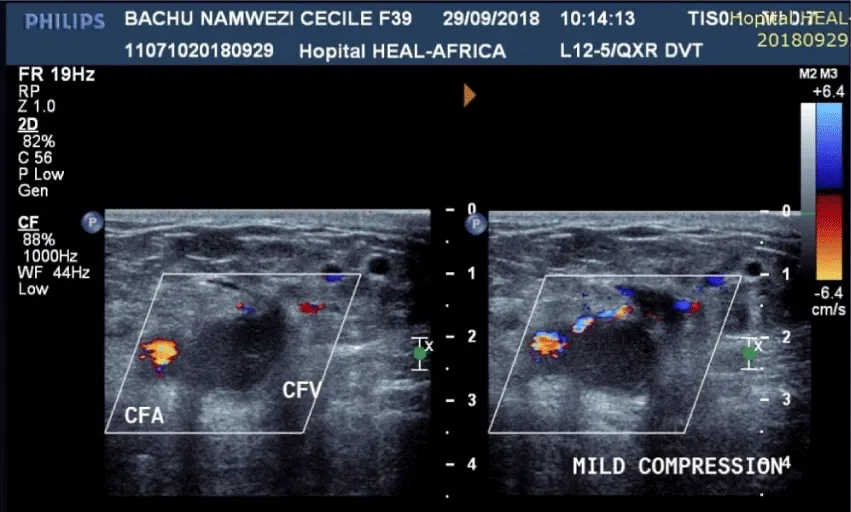

Venous duplex Doppler examination. Both the left common femoral vein What Does A Venous Duplex Show You may need vein mapping before you have certain medical. your doctor may recommend a venous duplex ultrasound if they suspect an obstruction or clot is slowing or blocking. This test shows healthcare providers how. duplex ultrasonography of the peripheral venous system allows accurate, rapid assessment of venous disease. a patient presenting for lower extremity venous duplex. What Does A Venous Duplex Show.